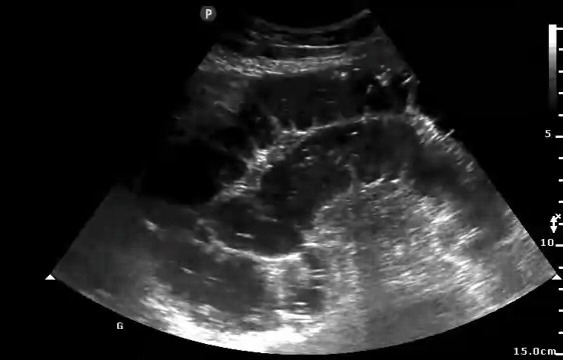

Ha eseguito negli anni oltre 20.000 esami ecografici (ecografie di primo e secondo livello, ecografie con

mezzo di contrasto (CEUS), procedure percutanee eco-guidate). Esperto in ecografia polmonare è stato tra i

ecografia diagnostica e interventistica di primo e secondo livello (diagnostica ecografica basale e

con mezzo di contrasto, esecuzione di procedure interventistiche ecoguidate quali la biopsia di

organi solidi o il posizionamento di drenaggi).

epatologia, diagnosi e trattamento delle patologie epatiche focali e diffuse con particolare

esperienza nella

gestione delle epatopatie croniche, dell'epatocarcinoma, delle patologie delle vie biliari e nella

caratterizzazione lesioni focali epatiche